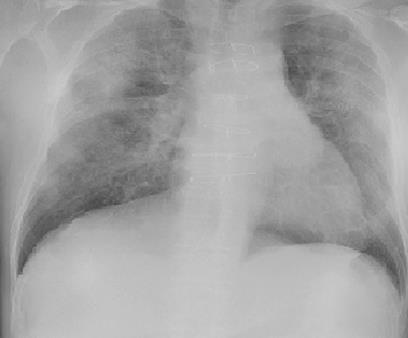

In medical image analysis, the expertise scarcity and the high cost of data annotation limits the development of large artificial intelligence models. This paper investigates the potential of transfer learning with pre-trained vision-language models (VLMs) in this domain. Currently, VLMs still struggle to transfer to the underrepresented diseases with minimal presence and new diseases entirely absent from the pretraining dataset. We argue that effective adaptation of VLMs hinges on the nuanced representation learning of disease concepts. By capitalizing on the joint visual-linguistic capabilities of VLMs, we introduce disease-informed contextual prompting in a novel disease prototype learning framework. This approach enables VLMs to grasp the concepts of new disease effectively and efficiently, even with limited data. Extensive experiments across multiple image modalities showcase notable enhancements in performance compared to existing techniques.